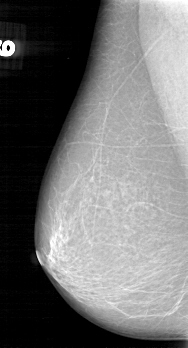

D_4042_1.RIGHT_CC

D_4042_1.LEFT_CC

RIGHT_CC LINES 5386 PIXELS_PER_LINE 3001 BITS_PER_PIXEL 12 RESOLUTION 43.5 NON_OVERLAY

FILE: D_4042_1.LEFT_CC.OVERLAY

TOTAL_ABNORMALITIES 1

ABNORMALITY 1

LESION_TYPE MASS SHAPE OVAL MARGINS OBSCURED

ASSESSMENT 0

SUBTLETY 5

PATHOLOGY BENIGN

TOTAL_OUTLINES 1

BOUNDARY